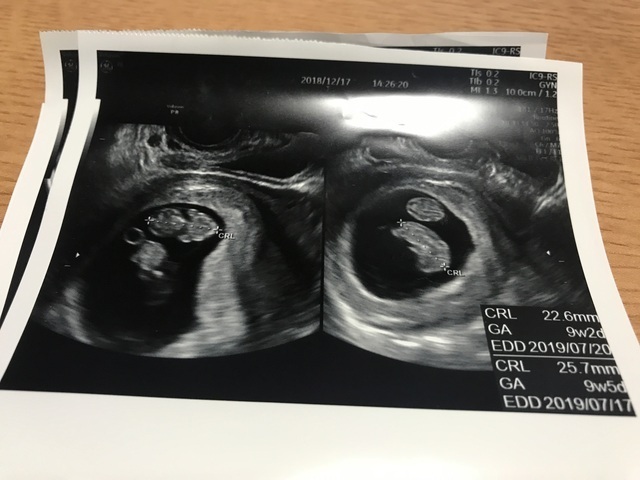

9週0日(9w0d・男の子・双子)|なおねこ さん(29歳)

エコー写真撮影時のエピソード:

妊娠9週目で双子と明らかに分かった写真です。

双子が欲しいと思っていたのでとてもびっくりしたし、初めての妊娠でびっくりと不安が入り混じった心境でした。また、病院も紹介された大学病院での初診だったのでとても緊張しました。